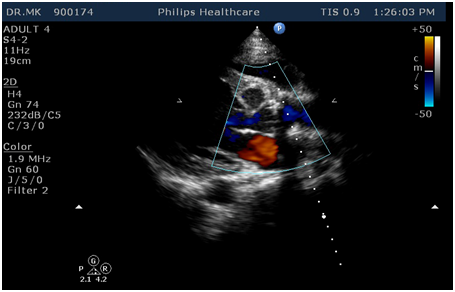

A 21 year old male was evaluated for Dyspnoea on Exertion NYHA class II since 3 months duration which progressed to class III for the past 2 weeks. On examination, he was thin built with height of 179cm. His blood pressure was 160/40 mmHg. There were no other features suggestive of Marfan Syndrome or any other connective tissue disorder. There was thrill present in the left 3 intercostal space just left of the sternum. Early diastolic murmur was well heard in the same area. Chest X-ray showed cardiomegaly. Echocardiogram revealed rupture of Left Sinus of Valsalva into the Left Ventricle, Moderate Aortic Regurgitation with global hypokinesia of left ventricle and severe Pulmonary artery hypertension. He was taken up for surgical repair of rupture sinus of valsalva and possible aortic valve repair. Intraoperative TEE showed moderate to severe Aortic regurgitation with no other intracardiac lesion but it was difficult to determine whether this was single or multiple ruptured sinus of Valsalva. Through midline sternotomy and after harvesting pericardium, Cardiopulmonary bypass was established with aortic and bicaval anastomosis. LV vent was placed through right superior pulmonary vein. The intraoperative examination through a transverse aortotomy revealed thickened and retracted tricuspid aortic valve with dilated aortic annulus with lack of central coaptation. There was about 20 X 15 mm defect in the left sinus of valsalva with about 2 cm length of wind-sock into left ventricle. The wind-sock was looking unhealthy and rupturing into the Left ventricle. The windsock was occupying the entire region of Aorto-Mitral Curtain. About 5X3 mm size defect was noted in the right sinus of Valsalva with dilated aortic annulus. Both the wind-sock was identified into the Left ventricle and its rupture was confirmed. Through aortic root the entire wind-sock from the left sinus was excised and it was closed directly using polypropylene sutures. The defect in the left sinus of valsalva was closed using appropriate size pericardial patch with Polypropylene suture. The additional rupture of sinus of valsalva in the right coronary sinus was closed directly using pledgetted polypropyle suture. On saline test we found that there mild central aortic regurgitation. We came off cardiopulmonary bypass after routine de-airing of the left side of the heart. TEE showed no residual shunt across the repaired sinus but there was persisting more than moderate aortic regurgitation with lack of central coaptation. In view of significant residual aortic regurgitation, we went back on Cardiopulmonary bypass and replaced the aortic valve with mechanical valve. The post-operative course was uneventful and the patient was discharged in healthy condition on the sixth post operative day. Pre-discharge Echocardiogram showed with no residual ruptured sinus of valsalva and well functioning prosthetic valve. On three months follow up, he is doing well and remains in NYHA class I (Figure 1).

Figure 1 2-D Echo with colour Doppler showing rupture of sinus valsalva from the left sinus.